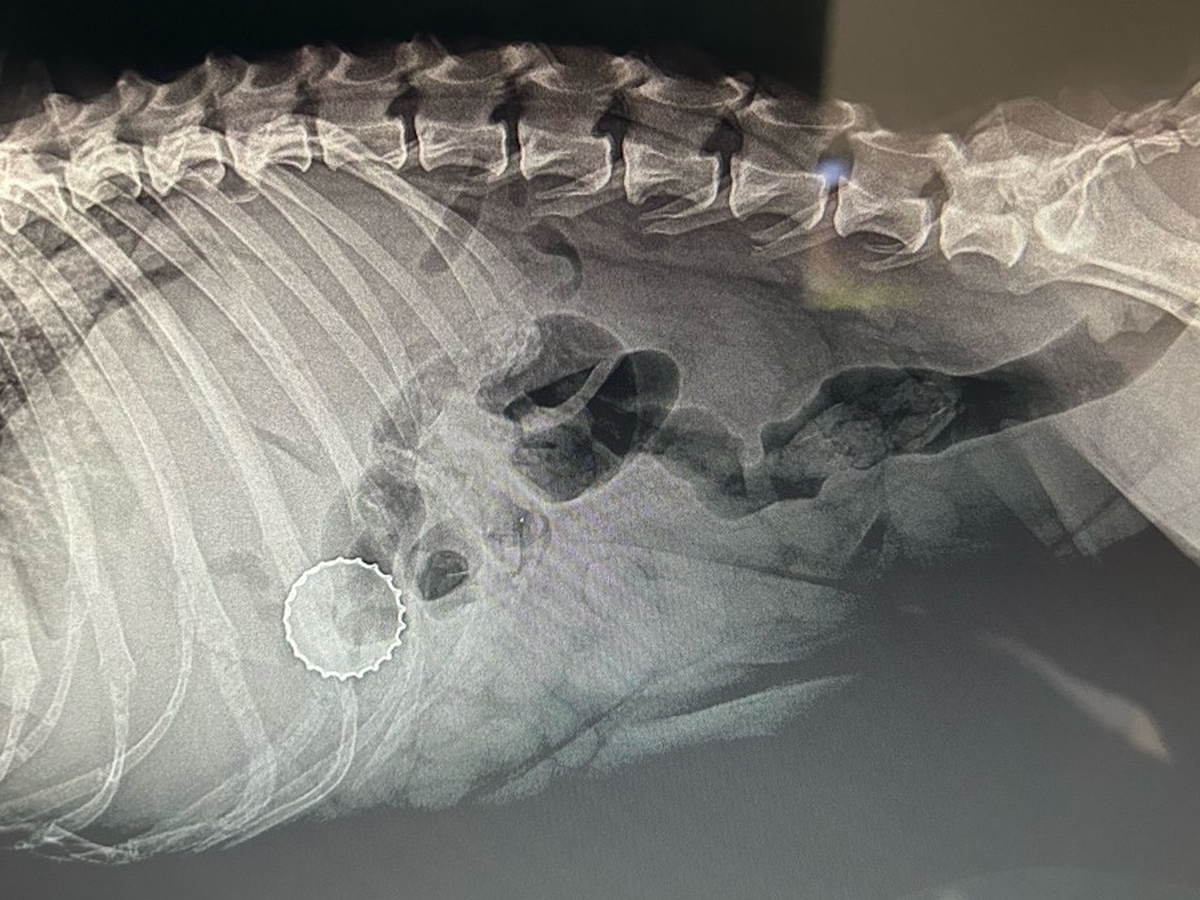

Chosen was found as a stray about a month ago and has been safe while waiting for her spay appointment. Today, during that visit, veterinarians discovered something shocking. Chosen has a bottlecap lodged inside her body.

This is a life threatening condition that requires immediate surgery. Her spay could not be performed because removing the bottlecap is now urgent. Without surgery, Chosen is at serious risk of infection, internal damage, and worse.